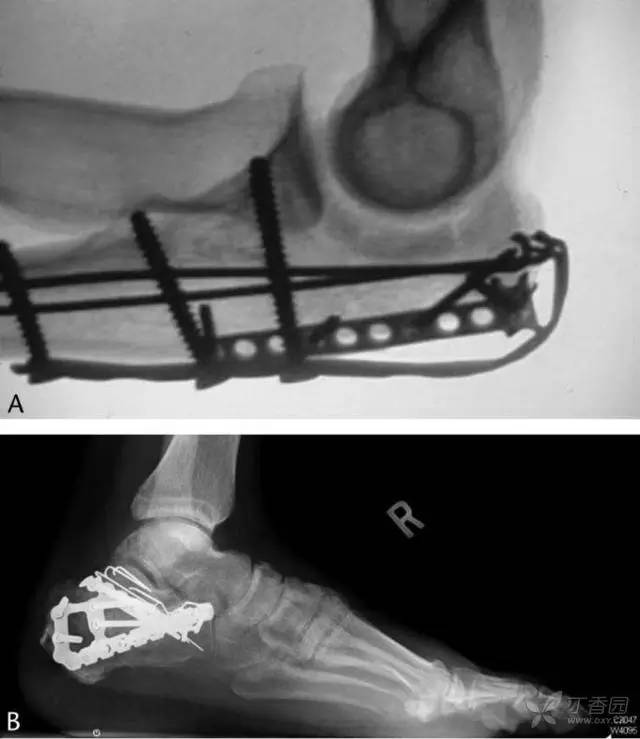

为了验证以上方法的有效性,研究人员对一组跟骨骨折的患者进行了随访。前瞻性地收集了 2008 年一整年中所有移位的跟骨骨折,共 56 例(51 位患者),其中 11 例没有采用克氏针固定,19 例随访不足一年。余下共 25 例(24 位患者)骨折共用了 86 根克氏针,全部采用上述方法折弯尾端。

术后至终末随访平均 2.26 年(12-46 个月)。X 线片显示无一例出现克氏针移位,也没有发生克氏针相关的疼痛。10 例患者由于钢板等原因需要拆除内固定物,这些患者共有 40 根克氏针均顺利拆除无任何并发症。

图 8 克氏针应用实例。A,鹰嘴骨折;B,跟骨骨折。